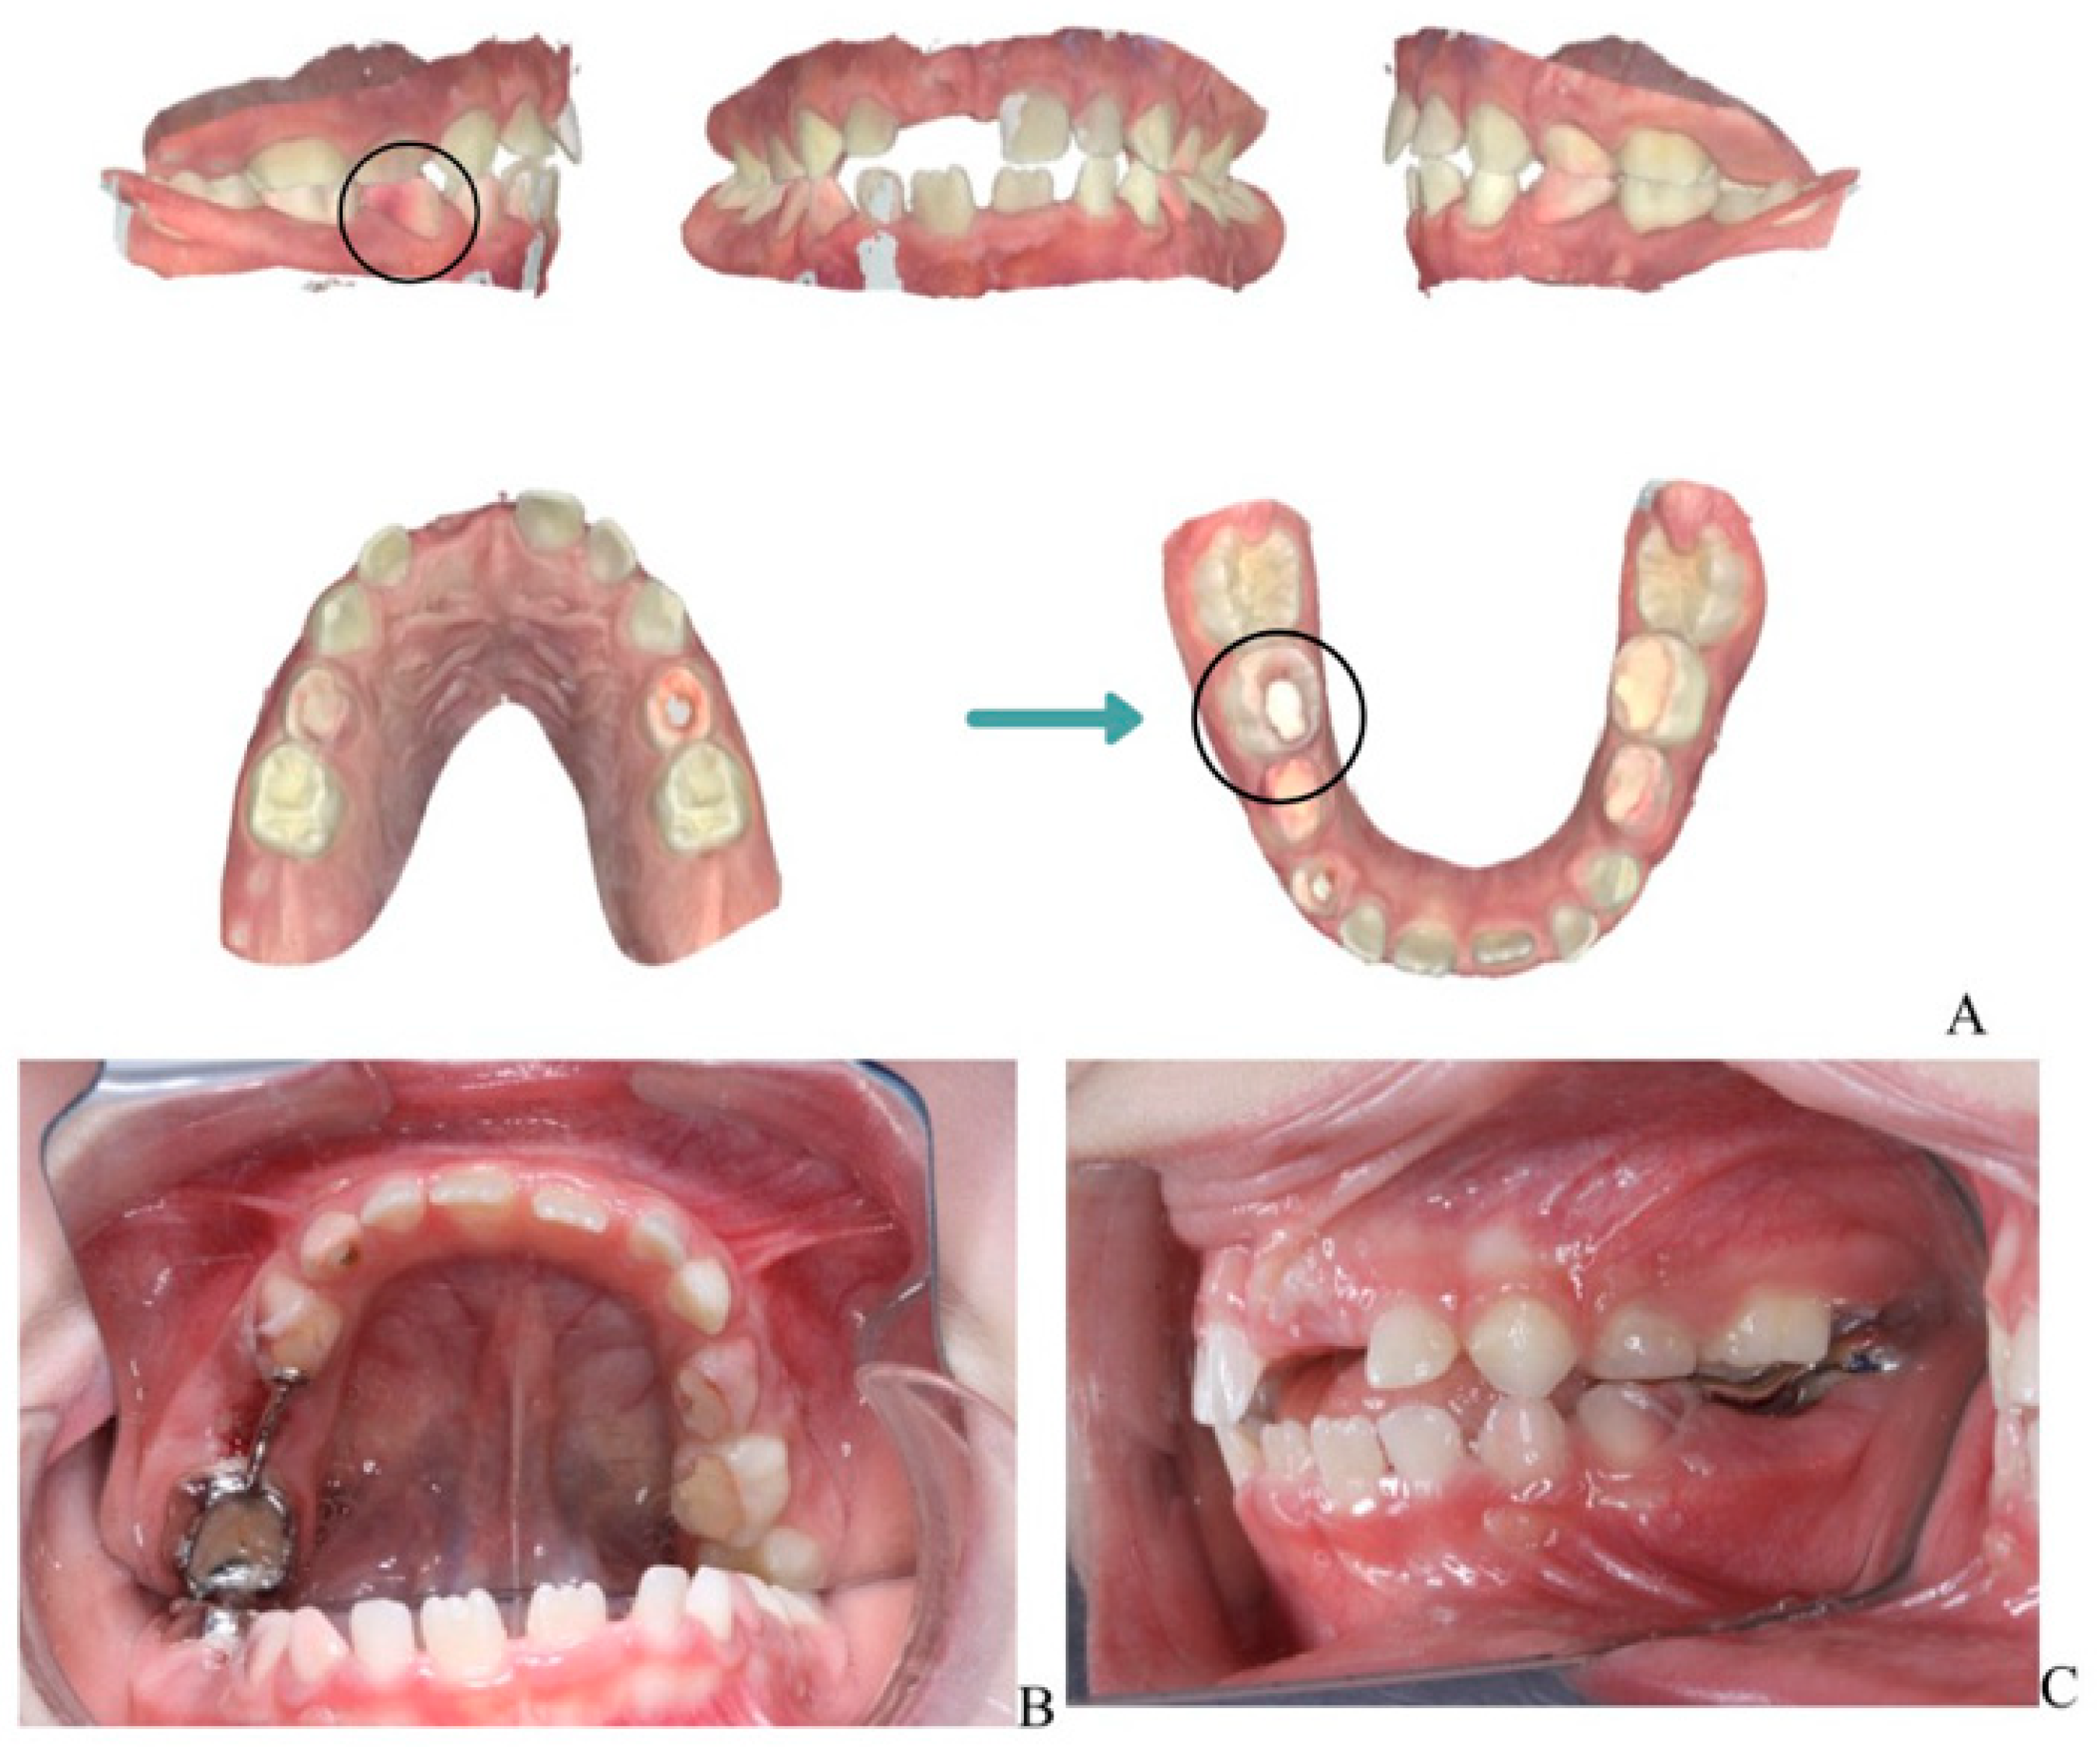

A laser-sintered digitally designed space maintainer was fabricated and cemented to preserve arch integrity and guide the eruption of the permanent successor (tooth 45) (Figure 3). Ongoing monitoring includes dental, biochemical, and renal assessments every 3–6 months.

Figure 3.

Orthodontic management following extraction of mandibular right second primary molar (tooth 85). (A) Scanned models of the dental arch showing the area of extraction and planned space maintenance. (B) Indirect intraoral mirror photograph showing the laser-sintered, digitally designed space maintainer cemented in situ to preserve arch integrity and guide eruption of the permanent successor (tooth 45). (C) Indirect intraoral mirror photograph showing a lateral view of the space maintainer, illustrating its position and adaptation to the adjacent teeth.